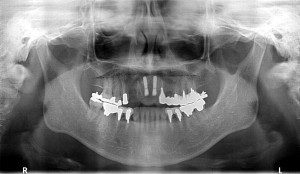

40歳代男性

右上1番から5番まで左上1番2番4番から7番まで欠損の男性でした。

CTを拝見すると、左側上顎洞底骨の厚みがなく、以前にサイナスリフトだけ

施術した人でした。

今日は、上顎に8本左下に1本に日本製AQBインプラント1回法を植え

させて頂きました。

次回は右下埋入させて頂きます。

術前

術後